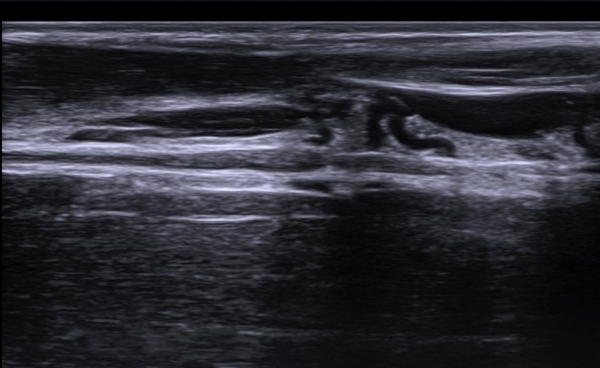

ÃÊÀ½ÆÄ ¼Ò°ß  : »ó¹Ú ³»Ãø ±ÙÀ°ÇǺνŰæ Ⱦ´Ü¸é°Ë»ç ¿¡¼­ ±ÙÀ°ÇǺνŰæÀÇ Àú¿¡ÄÚ ºÎÁ¾ÀÌ °üÂûµÈ´Ù(»çÁø 1).

Å½ÃËÀÚ¸¦ Á¶±Ý ¸»´ÜÀ¸·Î À̵¿ÇÏ´Ï ±ÙÀ°ÇǺνŰæÀÇ À§ÃàÀÌ °üÂûµÇ°í(»çÁø 2) ŽÃËÀÚ¸¦ Á¶±Ý ´õ